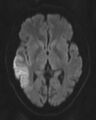

DWI showing restricted diffusion in the medial dorsal thalami consistent with Wernicke encephalopathy